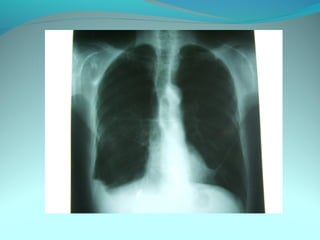

Cliché normal